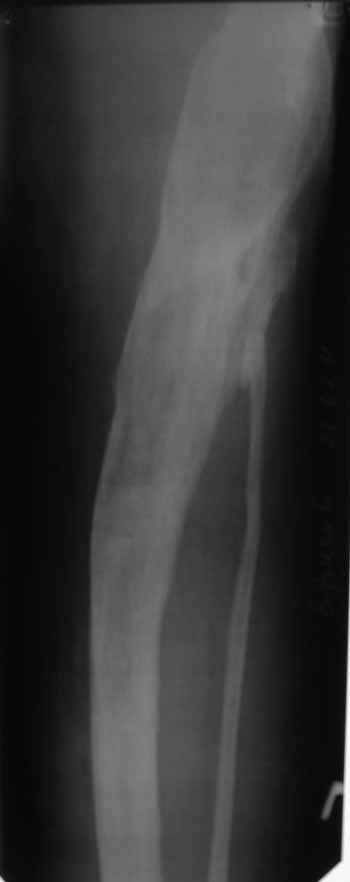

Пациент 29 лет. Неоднократно оперированная Coxa Vara.

В анамнезе этапные операции по поводу устранения Coxa Vara, формирование артродеза коленного сустава, удлинения бедра. В данный момент беспокоит укорочение 7 см, эквинус стопы. Объективно: - местный статус виден на фото, сосудистых и неврологических расстройств нет. Обратился в консультативном порядке, настроен на удлинение голени в г.Волгограде. (со слов больного - не берут без санации очага на голени). Ваши предложения? Из кулуарных соображений - а не актиномикоз ли это? Иссечение рубцов+ VAC+ Стержень с аппаратом + микрососудистый трансплантат(?)

Ваш вопрос, коллега, вполне правомерен. В советское время те из нас, кто занимался костно-гнойной инфекцией видели достаточное количество подобных несчастных, кочующих из стационара в стационар. Своеобразный госпитализм приводил к тому, что люди тратили всю свою, как правило достаточно короткую жизнь, на лечение зачастую реально неизлечимых процессов. В данном случае имеющаяся рентгенологическая картина груботрабекулярной перестройки кости, сочетающаяся с участками склероза говорит, скорее всего, о том, что вся имеющаяся картина, дополненная чудесными фотографиями,вполне укладывается в клинику гематогенного остеомиелита, которым и страдает пациент с детства. Никакие санации, к сожалению, не приведут в данном случае к излечению, так как все имеющиеся рубцы являются зоной жизни этой самой инфекции. При продолжении лечения не исключено достаточно раннее развитие амилоидоза в этом случае. Мне кажется, что оптимальным было бы определить пациента в институт протезирования и протезостроения или в то учреждение, которое в регионе выполняет данную функцию. Специалисты помогли бы определиться с уровнем ампутации, являющейся, по сути, единственным способом разорвть порочный круг и дать пациенту возможность какой-то социальной адаптации. А в плановом порядке, насколько мне известно, можно добиться неплохого финансового обеспечения под протез конечности по квоте. Другого решения здесь нет. С уважением, Андрей Волна

Про Курган - категорически отказывается, уже был, там пытались удлинять бедро, картина на фото..